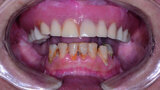

Fig. 1: Pre-op retracted view.